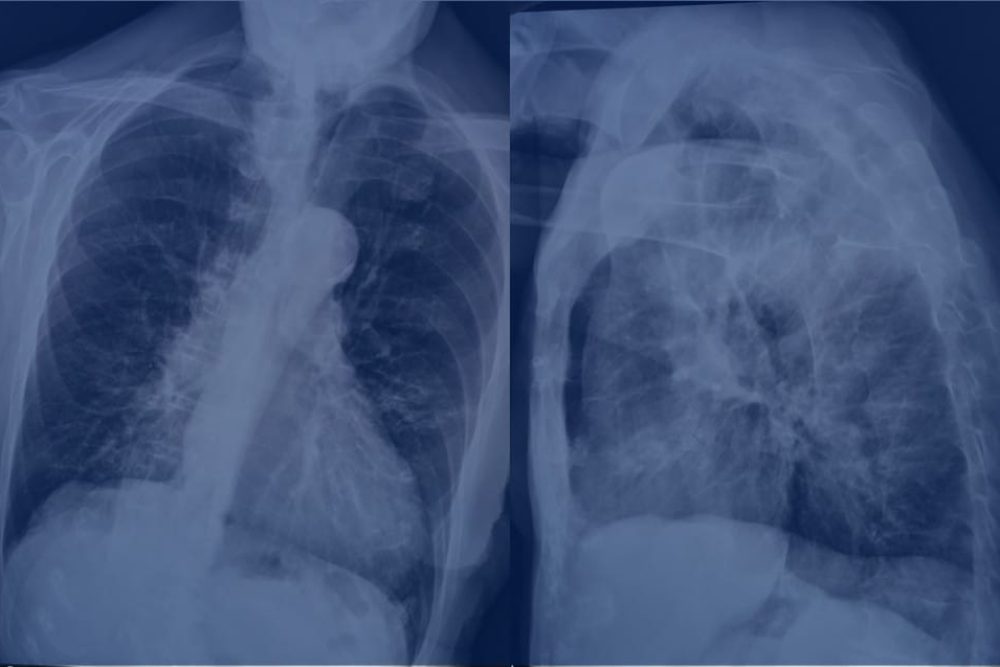

Nella malattia fisica, il processo anomalo ha come causa iniziale o provoca un difetto negli organi o in una funzione fisiologica: alcuni esempi sono il diabete, un cancro, la meningite.

2.2 Malattie croniche incurabili

La diagnosi di una malattia cronica, per la quale non è prevista alcuna cura, è motivo di preoccupazione che si accresce in proporzione alla gravità del quadro clinico. L’esistenza non sarà come prima, anche se solo a causa delle modifiche che bisognerà fare nello stile di vita: un piano di esercizi fisici, un’alimentazione particolare, dei farmaci, ecc. Se ci viene diagnosticato il diabete, dovremo seguire la dieta, magari usare l’insulina, fare frequenti test di controllo; in caso di ipertensione, problemi di colesterolo, insufficienza renale o cardiaca, dovremo ridurre il sale o i grassi, ecc.